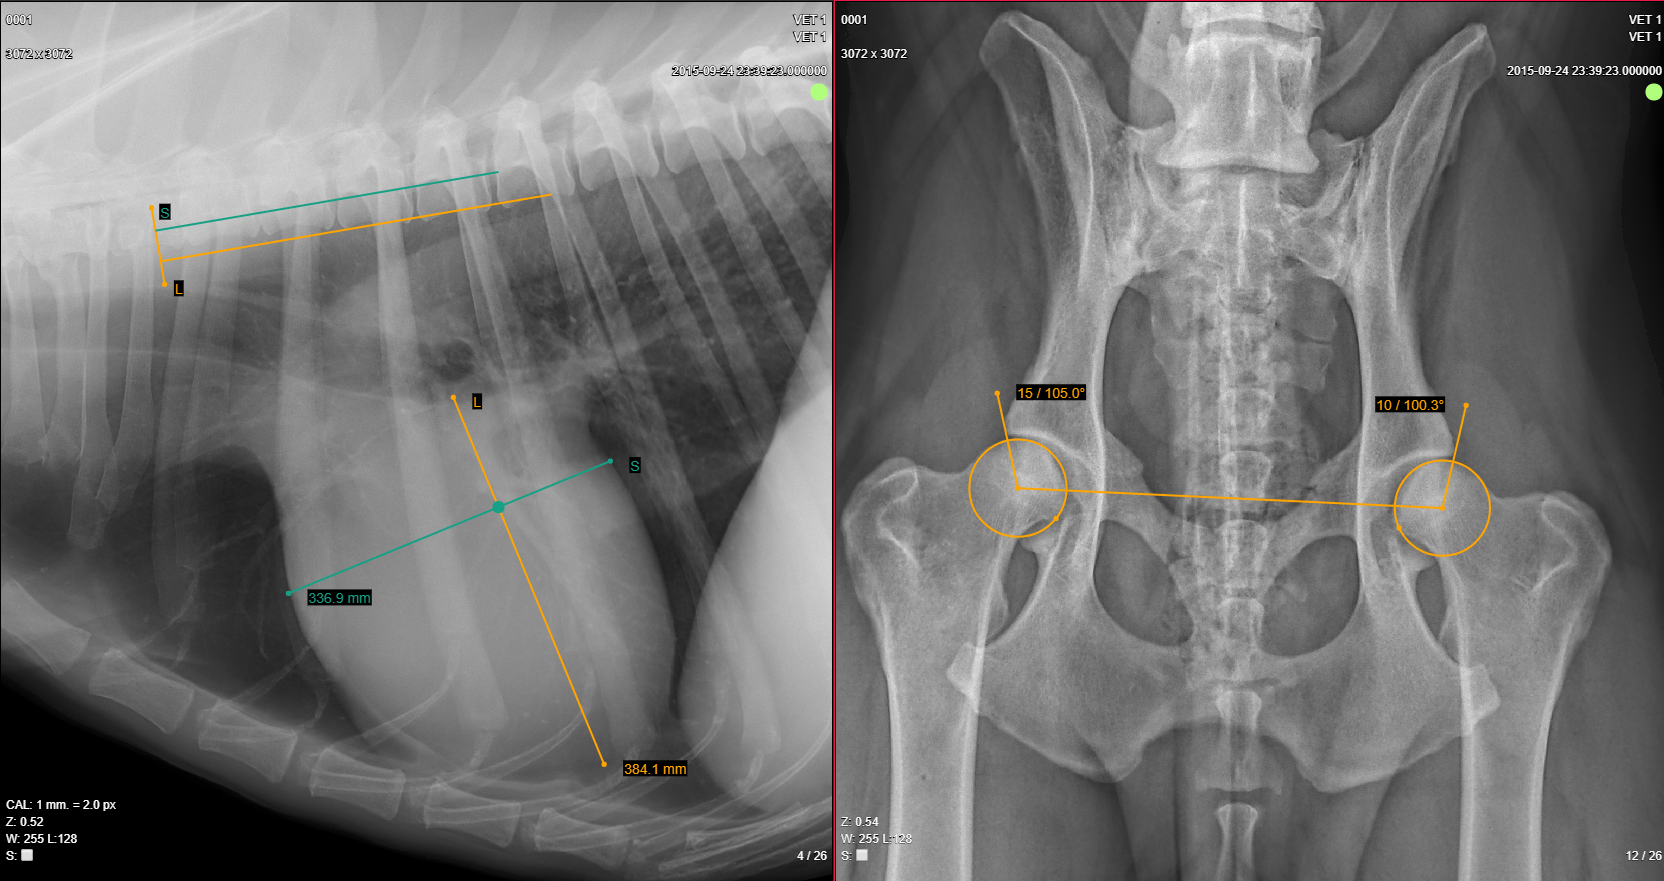

Measurements VHS and Norberg angle

The MedDream VET DICOM Viewer's specific measurements for veterinary field are:

• Cobb angle. Draw and measure a Cobb angle;

• Norberg angle. Measure a Norberg angle to evaluate canine hip dysplasia;

• VHS. Measure Vertebral Heart Score/Scale to asses cardiac enlargement;